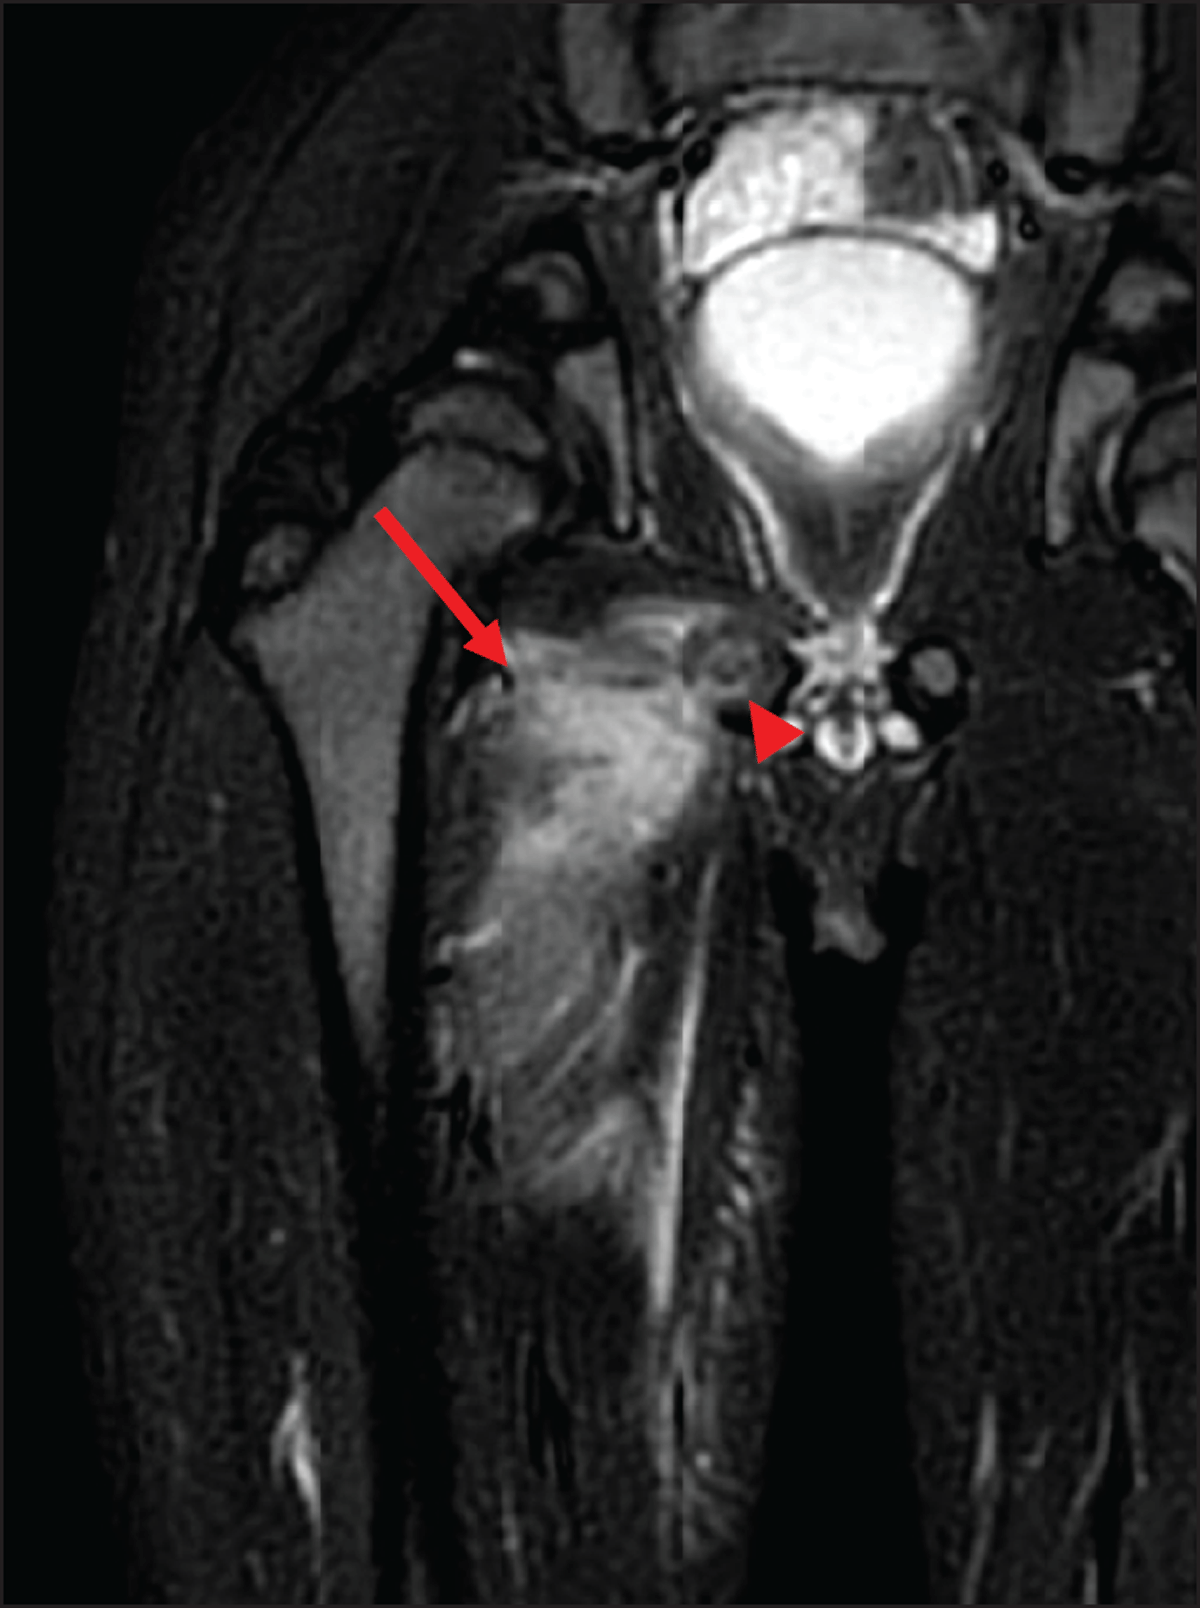

At this time, the blood analysis showed high white blood cells (18.500/mm3) and CRP (171.6 mg/L). Magnetic resonance imaging (MRI) (Figures 1, 2, 3) revealed a 3 cm long subperiosteal collection in contact with the right ischiopubic synchondrosis (arrowheads), suggestive of an abscess (arrows on axial. Figure 1, and coronal, Figure 2, post-contrast fat-saturated T1-weighted images). The abscess extended to the proximal part of adductors compartment and the right ischiopubic branch was involved by edema, appearing as high signal on short-tau inversion-recovery (STIR) imaging (Figure 3). Extensive edema was also visible in the surrounding tissues.

Figure 3